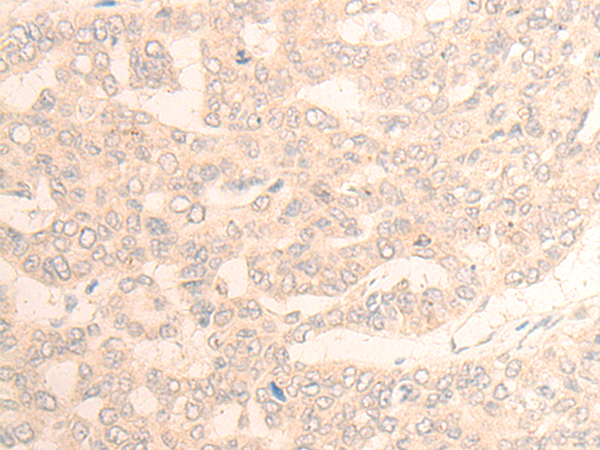

IHC positive control: |

Human liver cancer |

IHC Recommend dilution: |

20-100 |